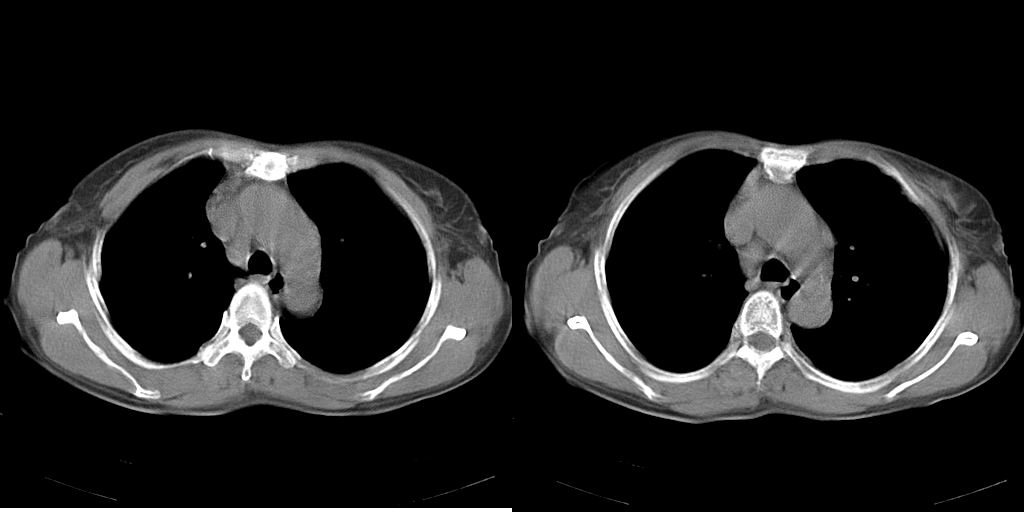

以下是引用dyqct在2007-1-23 15:01:00的发言:[br]左肺下叶实变、略萎陷,近肺门下部密度不均。上腔静脉后及隆突前见肿大淋巴结。余未见异常。[br]考虑:1、左肺下叶中心型肺癌伴肺不张、纵隔淋巴结转移;[br] 2、建议增强扫描并做任意平面重建确定肿块范围及支气管受累情况。

以下是引用同在2007-1-23 19:59:00的发言:[br]左肺下叶中央型肺癌伴肺不张及纵隔淋巴结转移.